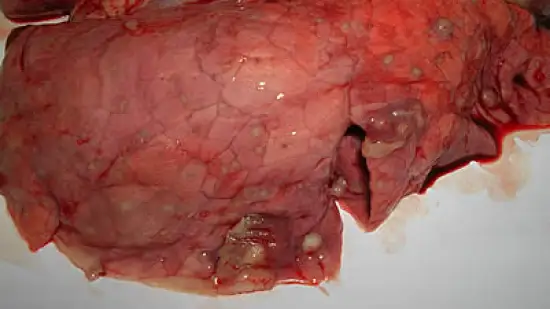

Ce poumon corespond à :